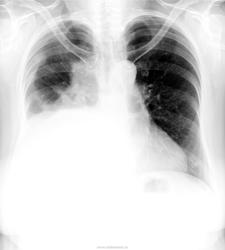

в категории указали "злокачественное образование", для которого зарактерен так называемый "холодный выпот" без температурной реакции. Должно быть затрудненное дыхание. Так как при таком большом выпоте нет смещения средостения в противоположную, следует думать об ателектазе (средняя доля?)

Осумкованный выпот справа. Свободная жидкость в плевральной полости тоже есть. Должна быть одышка. Если есть отёки на ногах - сердечная недостаточность. Ещё много причин, вызывающих скопление жидкости в плевральной полости, в том числе онко, сдавление полой вены.

Как Вам, коллеги, тень в верхней доле справа?Смещения нет, ателектаз, вероятно. компенсирует выпот.Лёгочных жалоб, отёков и лихорадки нет.

Вы абсолютно правы, тут ателектаз + выпот. Выпот за счет Мт в верхних отделах, м.б. и в паракостальную плевру.  Думаю не только средняя доля, а весь центральный бронх.